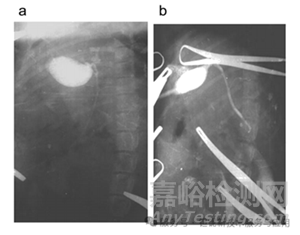

犬膽道造影中,30% 稀土TaO?可清晰顯示直徑≥7 mm 的結(jié)石,肝內(nèi)膽管分支顯影分辨率達(dá) 0.5 mm(圖 9)。相比之下,泛影葡胺組黏膜出現(xiàn)大面積壞死,而 稀土TaO?組僅見輕度淋巴細(xì)胞浸潤(圖 10、圖 11)。

圖9.使用10% (a,b)、20% (c,d)和30 % (e,f)placeLOT凝膠混懸液對(duì)犬進(jìn)行術(shù)中膽囊膽管造影。相同圖像放大4倍(b,d,f)。

圖10.犬膽囊注射LOT 30 %凝膠混懸液后,蘇木精和伊紅染色,100倍放大。

圖11.狗的膽囊在注射尿路造影劑后。蘇木精和伊紅染色。100倍放大。